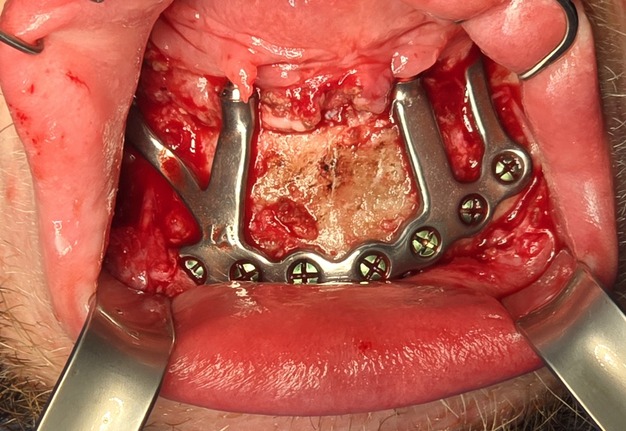

Under general anesthesia in an operating room setting, a crestal incision with bilateral releasing incisions was made on the mandible. Subperiosteal dissection extended to the inferior border of the mandible while preserving both mental nerves. A CAD-CAM bone reduction guide was rigidly fixated and used to perform alveoloplasty and predict fixation sites.

The custom titanium framework was trial seated and adapted accurately.

Due to the patient’s trismus, a transbuccal trocar system was used bilaterally to access posterior fixation sites, a technique commonly used in limited access mandibular fixation [17]. Locking screws were. placed under copious irrigation to achieve rigid stabilization (Fig 8).